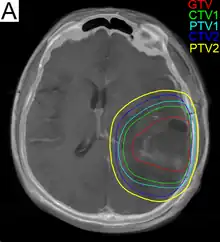

Radiotherapy

Subsequent to surgery, radiotherapy becomes the mainstay of treatment for people with glioblastoma. It is typically performed along with giving temozolomide.[10] A pivotal clinical trial carried out in the early 1970s showed that among 303 GBM patients randomized to radiation or best medical therapy, those who received radiation had a median survival more than double those who did not.[69] Subsequent clinical research has attempted to build on the backbone of surgery followed by radiation. Whole-brain radiotherapy does not improve when compared to the more precise and targeted three-dimensional conformal radiotherapy.[70] A total radiation dose of 60–65 Gy has been found to be optimal for treatment.[71]